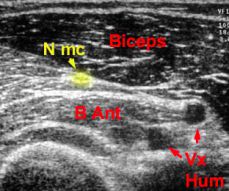

Une Compression symptomatique du Nerf Musculo-cutané peut être observé lors de la pratique sportive.

1/ compression lors de sa traversée du coraco-brachial

- étirement compression du nerf, lors de la mise en abduction-rotation externe du bras (tennis, volley, basket, baseball....)

- compression directe par la contraction musculaire isométrique et répétée du muscle coraco-brachial (motard, musculation, natation)